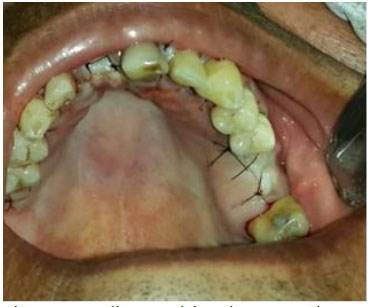

Artigo De Revisao Carie Precoce E Severa Na Infancia Uma Abordagem Integral Doi 10 2223 Jped 1908 Estela M Lossoi Maria Cristina R Tavaresii Juliana Y B Da Silvaiii Cicero De A Urbaniv Icirurgia Dentista Doutora Odontopediatria Professora